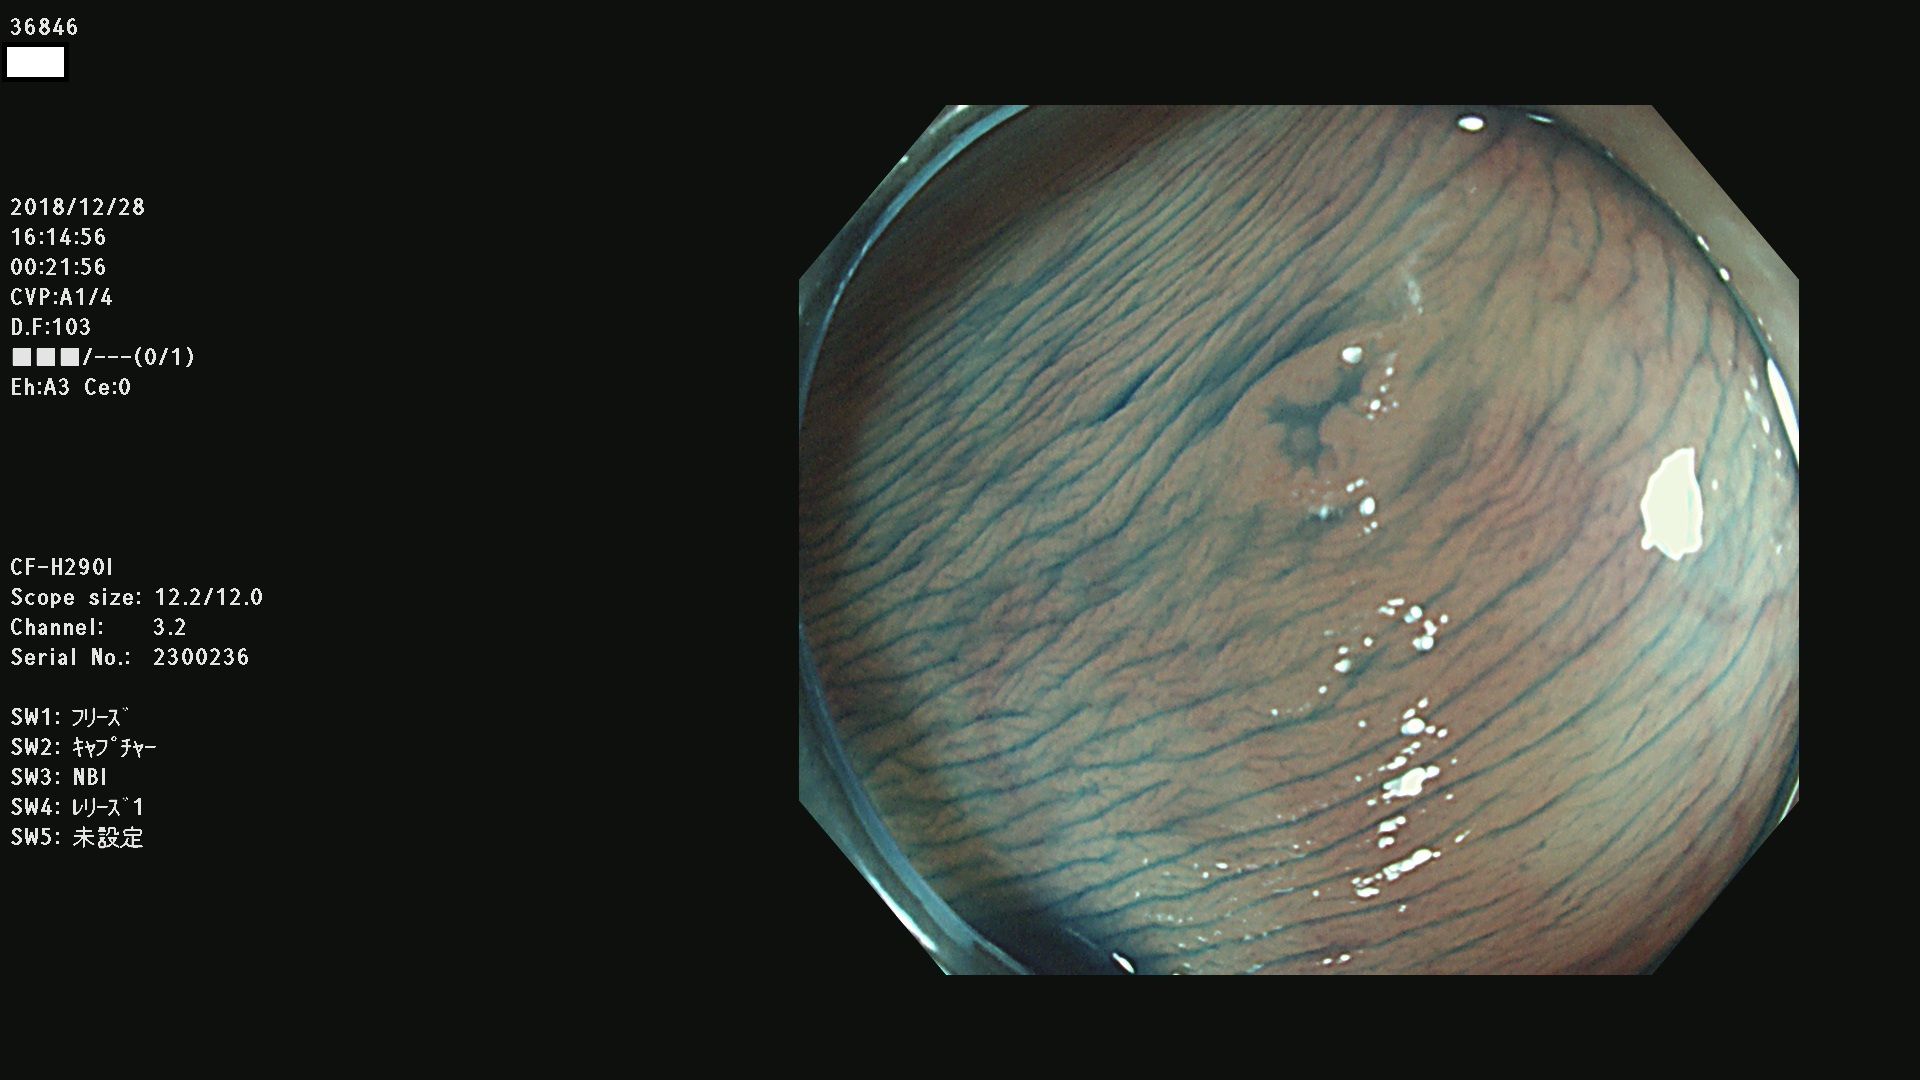

36804 36806 36807 36808 36809 36810 36811 36813 36815 36816 36817 36818 36820 36821 36822 36824 36825 36826 36828 36829 36830 36831 36832 36833 36834 36835 36837 36840 36841 36842 36845 36846 36848 36849 36851 36852 36853 36854 36855 36857 36859 36860 36861 36862(SSAPのみ) 36863 36864 36866 36868 36869 36870 36873 36875 36877 36878 36879 36881 36882 36883 36884 36885 36886 36887 36888 36889 36891 36892 36893 36894 36895 36896 36897 36898 36899

発見困難で危険性の高い平坦型病変(上記100名より抽出)